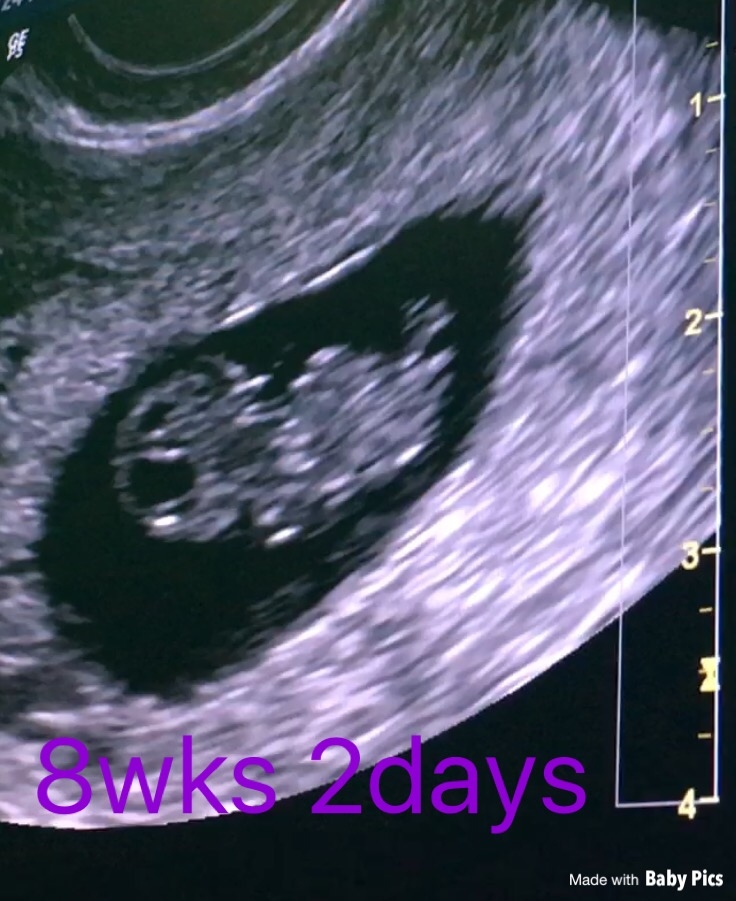

Post your ultrasound pics.

our little peanut on Thursday